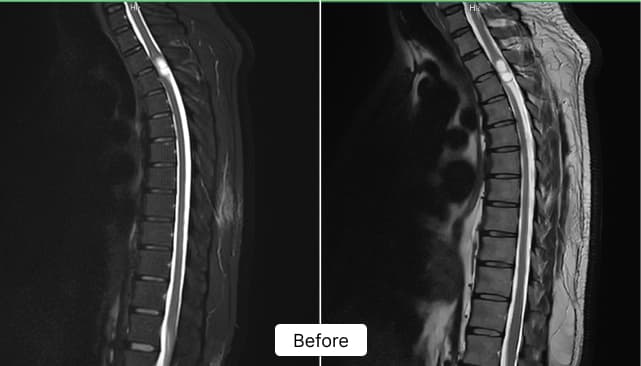

Diagnostic Imaging & Early Diagnosis:

MRI revealed a 22 × 12 × 11 mm tumor at the D2–D3 level, compressing the spinal cord and causing progressive neurological symptoms.